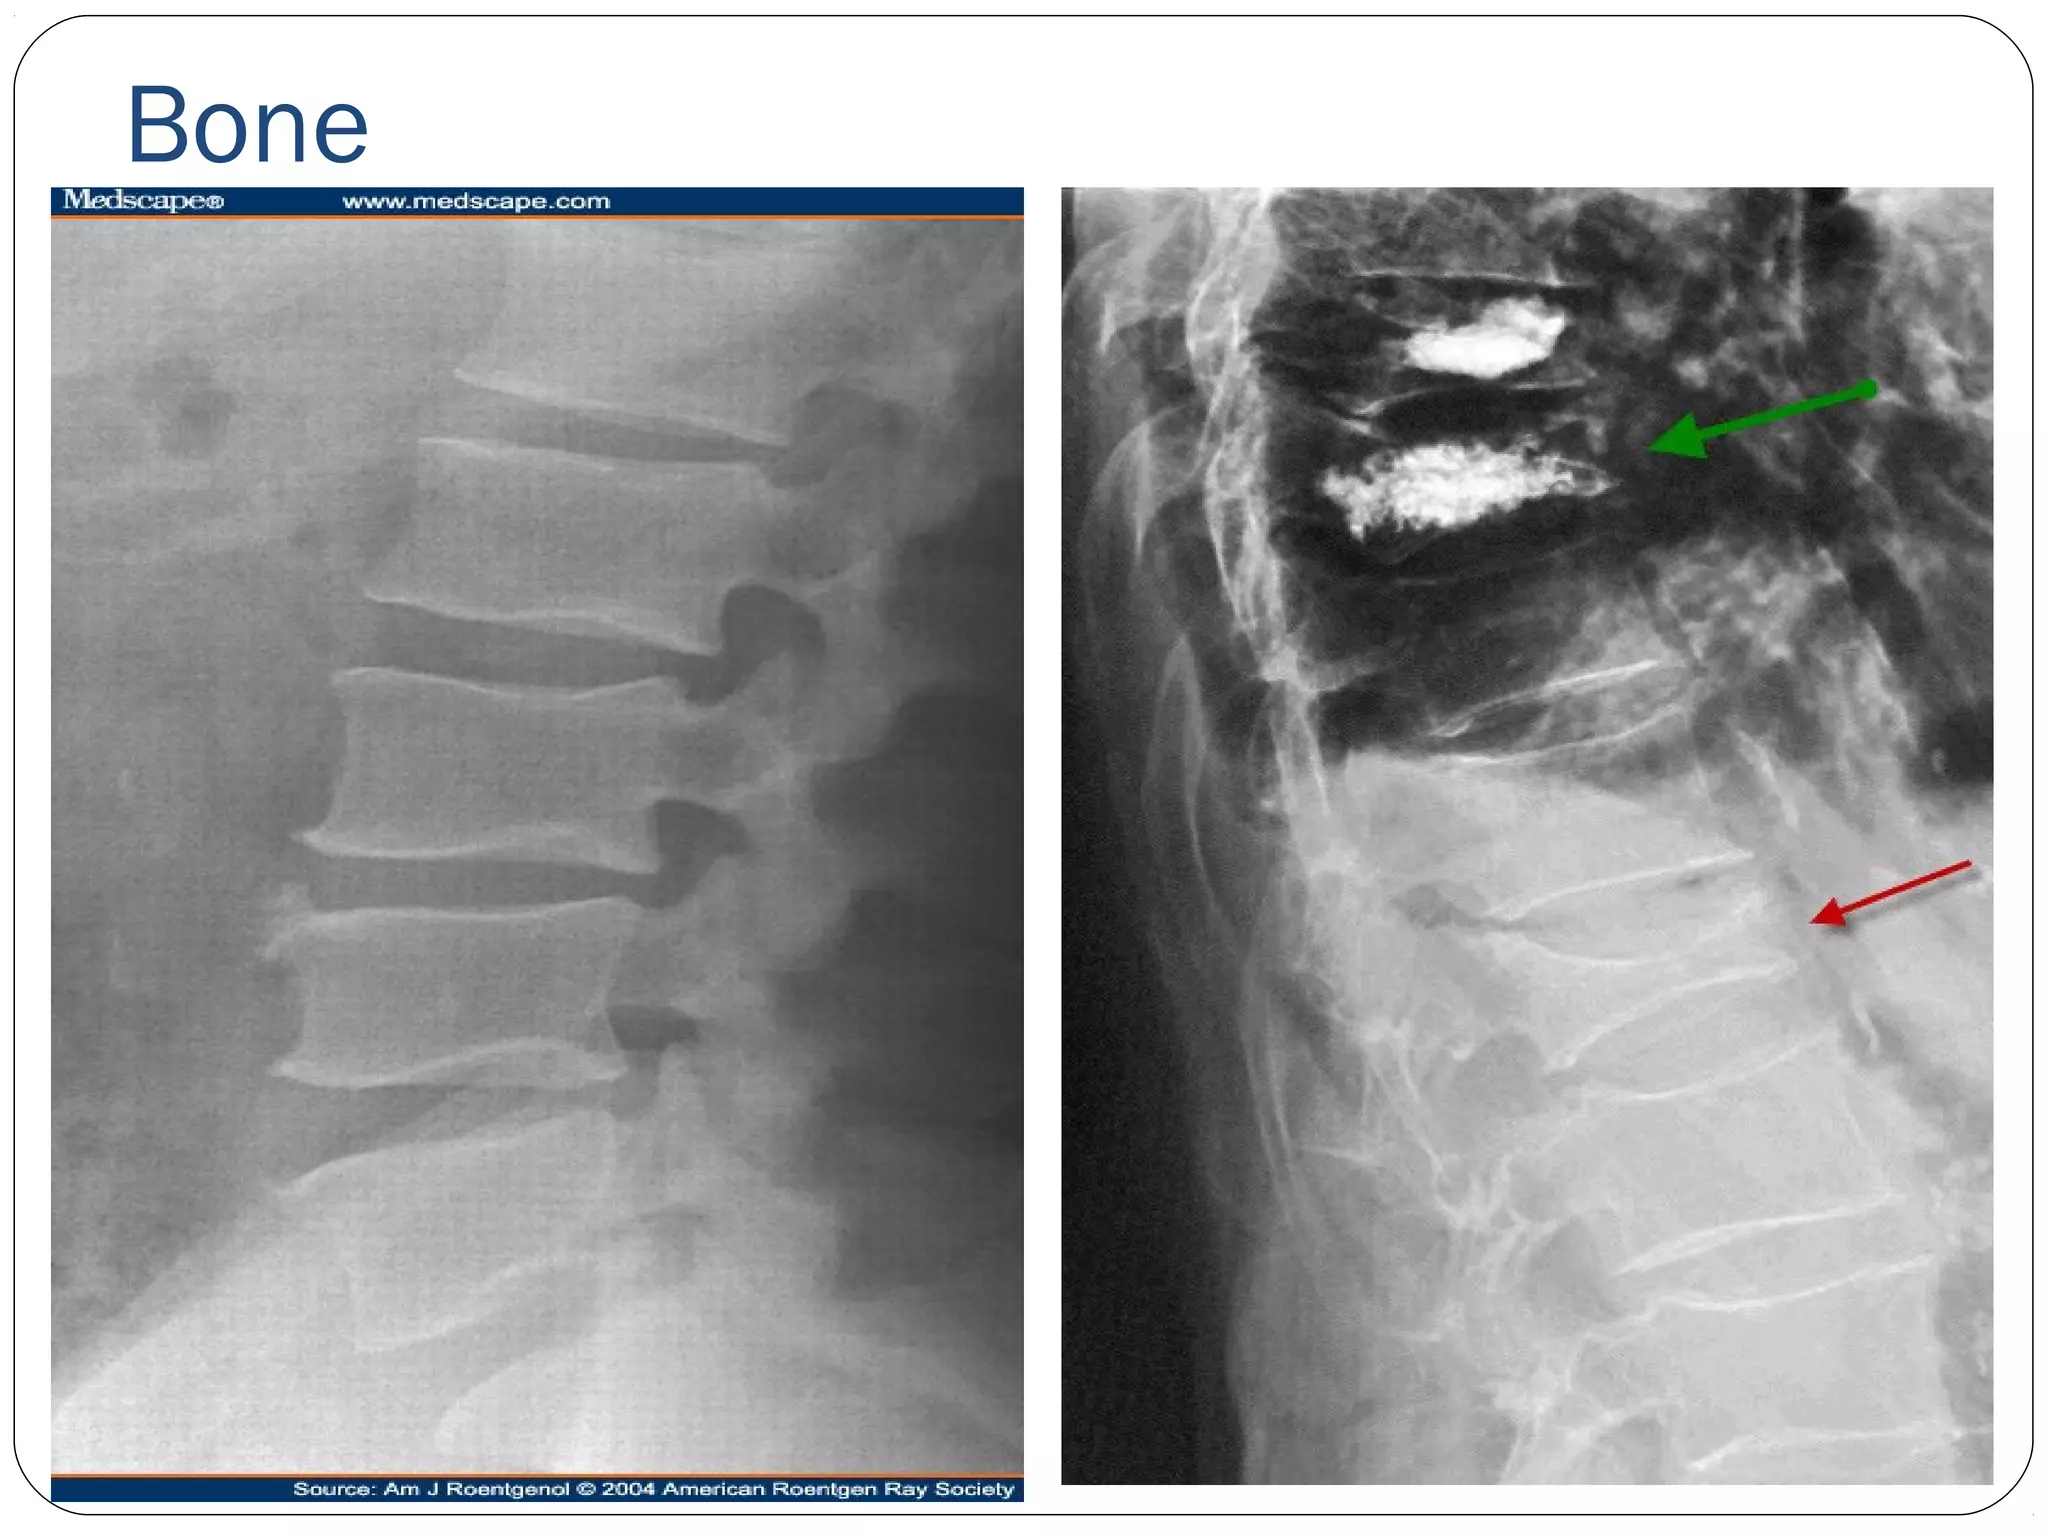

Bone